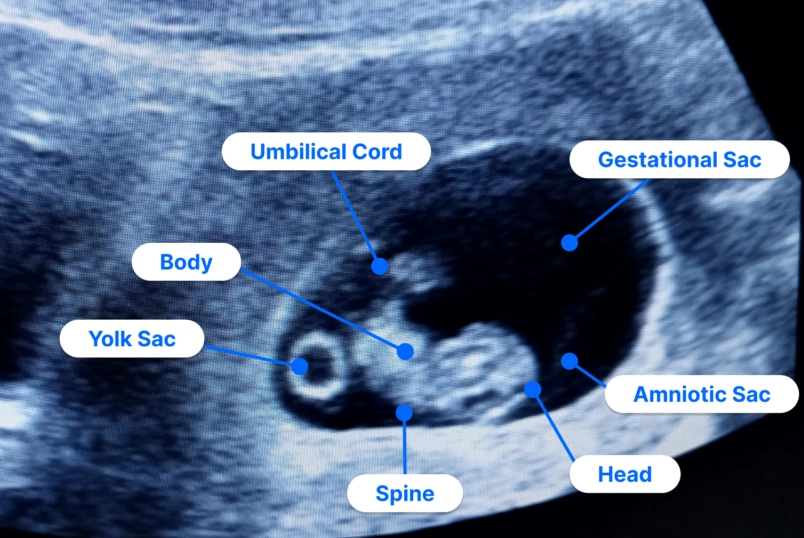

After all this talk of signs and symptoms, remember the bigger picture. A normal pregnancy isn't defined by a perfect checklist of symptoms. It's defined by the healthy progression confirmed through your prenatal appointments: steady weight gain, a growing fundal height (the measurement of your belly), a strong fetal heartbeat, and normal ultrasound findings.